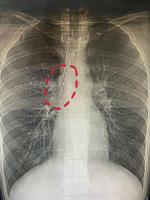

特朗普:我一直知道北约是纸老虎 考虑退出北约特朗普,我一直知道北约是纸老虎2026-04-02 11:44:24 美国在伊朗最好使的武器,是抄伊朗的:逆向工程无人机美国在伊朗最好使的武器,是抄伊朗的…2026-04-02 11:43:18 80多场发布会背后,车圈“容不下17个董事长” 生存之战白热化80多场发布会背后,车圈容不下17个董事长2026-04-02 11:41:04 美媒直言美国陷伊朗死局 军事神话破灭美媒直言美国陷伊朗死局2026-04-02 10:22:37 特朗普:伊朗战事取得压倒性胜利 核心目标接近完成特朗普,伊朗战事取得压倒性胜利2026-04-02 09:45:07 就海湾和中东局势 中巴提出五点倡议 共促地区和平稳定就海湾和中东局势中巴提出五点倡议2026-04-02 09:44:08 全球资产突发巨震 地缘冲突引发市场动荡全球资产突发巨震2026-04-02 11:29:35 美军要对伊朗440公斤高浓铀动手了 行动复杂风险极高美军要对伊朗440公斤高浓铀动手了2026-04-02 10:49:52 特朗普宣布“胜利” 但还要猛打2到3周 对伊朗持续施压特朗普宣布胜利但还要猛打2到3周2026-04-02 09:57:32 17岁小伙征兵体检发现肺上有根针 胸腔藏针十余年17岁小伙征兵体检发现肺上有根针2026-04-02 11:34:20 英法等十国外长,联合发声 呼吁黎以直接谈判英法等十国外长,联合发声2026-04-02 10:06:32 特朗普称对伊战事核心目标接近完成 美军取得显著优势特朗普称对伊战事核心目标接近完成2026-04-02 10:21:11 农历二月十五满月迎福 传统习俗祈福纳祥农历二月十五满月迎福2026-04-02 11:38:09 章小蕙李若彤关于优思益致歉 明星带货翻车章小蕙李若彤关于优思益致歉2026-04-02 11:37:28 伊朗以色列同时大规模互袭 导弹密集对攻升级伊朗以色列同时大规模互袭2026-04-02 11:04:59 美国在伊朗最好使的武器,是抄伊朗的:逆向工程无人机美国在伊朗最好使的武器,是抄伊朗的…2026-04-02 11:43:18 美国绕月火箭宇航员一度与地面失联 星链卫星故障引担忧美国绕月火箭宇航员一度与地面失联2026-04-02 11:15:22 巴菲特透露一笔“小额”新买入 仍深度参与投资决策巴菲特透露一笔小额新买入2026-04-02 09:37:47 阿尔忒弥斯2号 50年后再启月球征程阿尔忒弥斯2号2026-04-02 09:44:48 金饰克价涨到1456元 金价持续攀升金饰克价涨到1456元2026-04-02 11:36:09 美国要求北约将爱国者导弹调往中东 补充告急弹药库美国要求北约将爱国者导弹调往中东2026-04-02 09:33:31 俄方说伊朗最高领袖目前身在伊朗 避免公开露面俄方说伊朗最高领袖目前身在伊朗2026-04-02 09:48:29 战火灼烧以色列 真主党深入侵袭引发大规模疏散战火灼烧以色列2026-04-02 10:36:50 80多场发布会背后,车圈“容不下17个董事长” 生存之战白热化80多场发布会背后,车圈容不下17个董事长2026-04-02 11:41:04 美媒:特朗普要跑路了,盟友被迫买单,还留下一个更危险的伊朗 中东棋局失控美媒,特朗普要跑路了,盟友被迫买单,还留下一个更危险的伊朗2026-04-02 10:06:51 张雪想卖陈光标赠的豪车给嫣然捐款 为国争光获赠车张雪想卖陈光标赠的豪车给嫣然捐款2026-04-02 11:33:09 曝短剧男顶忘本:走红后抹杀团队付出、立虚假老实人设曝短剧男顶忘本2026-04-02 11:39:24 张雪为创业向亲戚朋友借了几百万 春节曾是张雪最难熬的日子 张雪为创业向亲戚朋友借了几百万2026-04-02 11:26:30 伊朗最高领袖首次讲话 重申封锁霍尔木兹海峡伊朗最高领袖首次讲话2026-04-02 09:35:05 绿电概念表现回暖 政策与地缘因素助力绿电概念表现回暖2026-04-02 11:28:28 乒乓球世界杯:覃予萱首局反败为胜!4-8到11-9,领先33岁老将!覃予萱冲击女单8强2026-04-02 11:24:39 张雪想卖陈光标赠送豪车给嫣然捐款 彰显实力与骨气张雪想卖陈光标赠送豪车给嫣然捐款2026-04-02 11:35:41 上半年假期扎堆到来 家庭自驾游需求高涨上半年假期扎堆到来2026-04-02 11:30:13 广东顺德“莫氏鸡煲”意外爆红 老板欲休半月避热潮广东顺德莫氏鸡煲意外爆红2026-04-02 11:37:53 特朗普:我一直知道北约是纸老虎 考虑退出北约特朗普,我一直知道北约是纸老虎2026-04-02 11:44:24